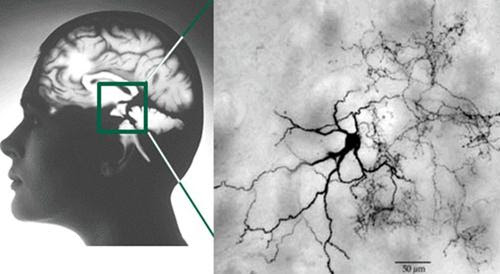

Bệnh Parkinson phát triển khi một nhóm nhỏ tế bào thần kinh không hoạt động được bình thường. Vị trí của các tế bào này chỉ được biết vào năm 1950, khi một chất màu xám nằm trong não giữa bị bệnh. Sau khi xác định được chất dẫn truyền thần kinh mới là dopamine được tìm ra và có trong chất xám này cùng các tế bào gốc của não, việc tìm cách điều trị bệnh Parkinson bắt đầu.

Cùng khi đó, khoa học cũng tìm ra tác dụng phụ của các thuốc thần kinh mới, reserpine và nhóm các thuốc phenothiazine: thuốc này có vẻ như gây ra các triệu chứng của bệnh Parkinson. Và vì thuốc này can thiệp vào sự có mặt của dopamine tại đoạn cuối của dây thần kinh, người ta nghĩ rằng có sự liên hệ giữa dopamine và bệnh Parkinson. Vì một lý do nào đó, các tế bào trong chất xám người bệnh Parkinson không cung cấp đủ dopamine để gửi các tín hiệu thần kinh tới não bộ và do đó có các cử động bất thường của cơ bắp.

Hiện nay các nghiên cứu y học về bệnh Parkinson đều tập trung vào việc tìm ra bệnh sớm và cấy các yếu tố di truyền. Đã có một số ánh sáng rằng hóa chất như chất có hại cho thần kinh methyl phenyl tetrahydropyridine có một vai trò nào đó trong triệu chứng của bệnh giống như bệnh Parkinson. Các thí nghiệm trong giữa năm 1980 chứng tỏ rằng MPTP đã phá hủy một số tế bào thần kinh ở vùng xám. Và vào giữa năm 1990, một số nhỏ bạn trẻ ở Hoa Kỳ đã bị Parkinson sau khi dùng các chất gây nghiện như heroin đã bị pha lẫn với MPTV.